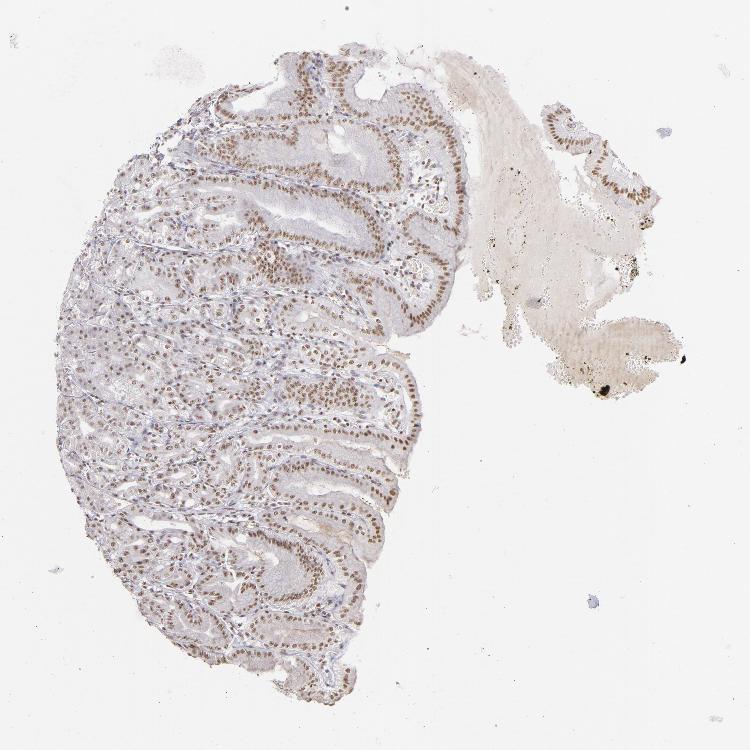

STOMACH 1 - Antibody stainingi

Antibody staining in the annotated cell types in the current human tissue is reported as not detected, low, medium, or high, based on conventional immunohistochemistry profiling in selected tissues. This score is based on the combination of the staining intensity and fraction of stained cells.

Each image is clickable and will lead to virtual microscopy that enables deeper exploration of all samples and also displays staining intensity scores, fraction scores and subcellular localization as well as patient and tissue information for each sample.

Antibody HPA008736Antibody CAB002224Antibody CAB025546

Glandular cells HighMediumMedium